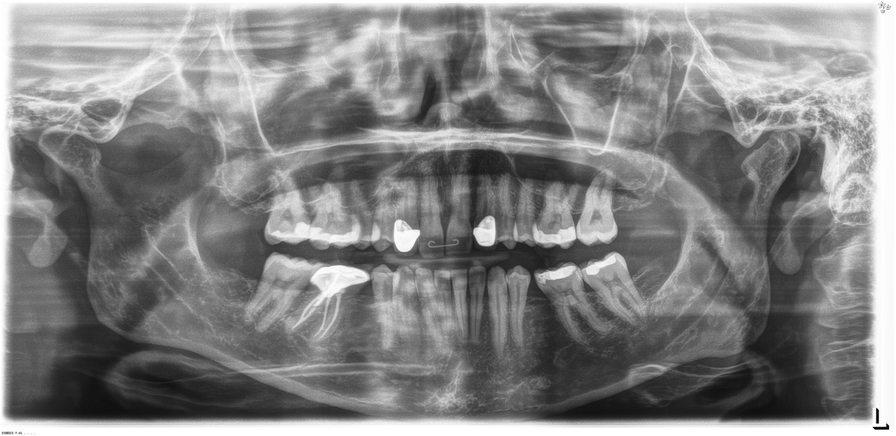

Fig. 3

Panoramic Dental Radiograph. Panoramic dental radiograph from our proband with a pathogenic AXIN2 variant. There are 24 teeth. A complete set of adult is 32 teeth. The patient is lacking her upper lateral incisors, bottom second premolars, and 3 third molars (wisdom teeth)